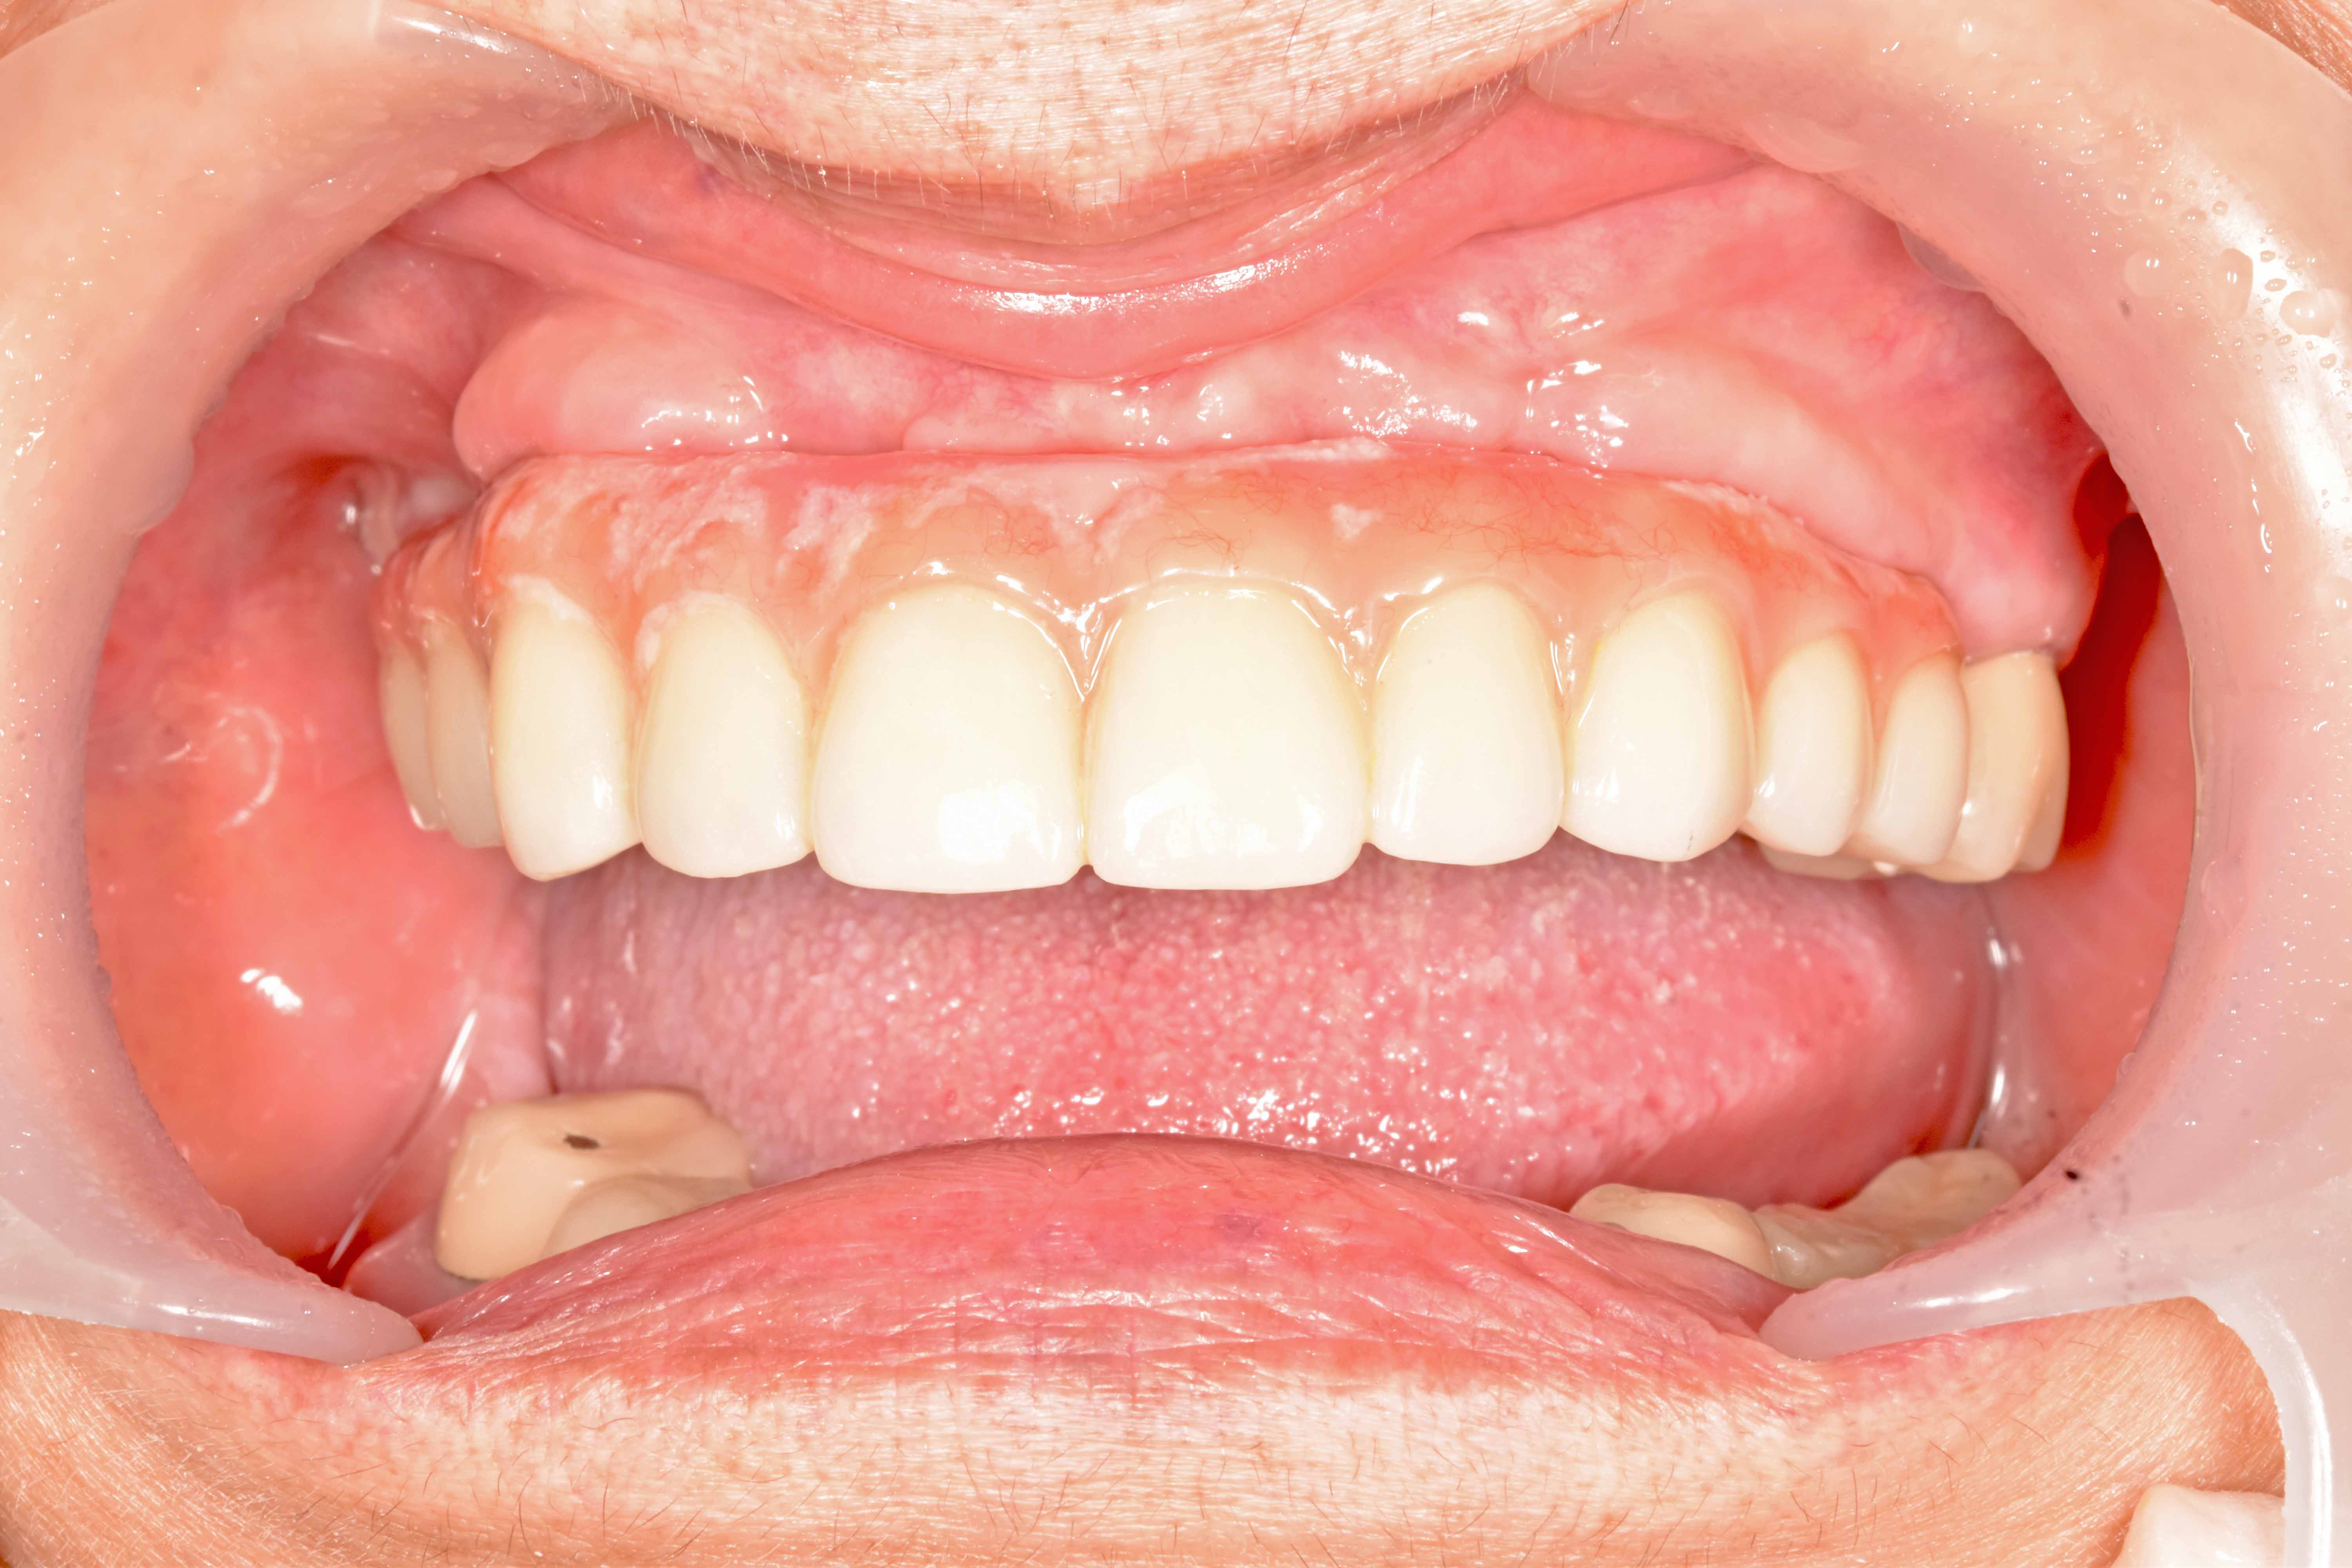

鎖上正式假牙

完成!